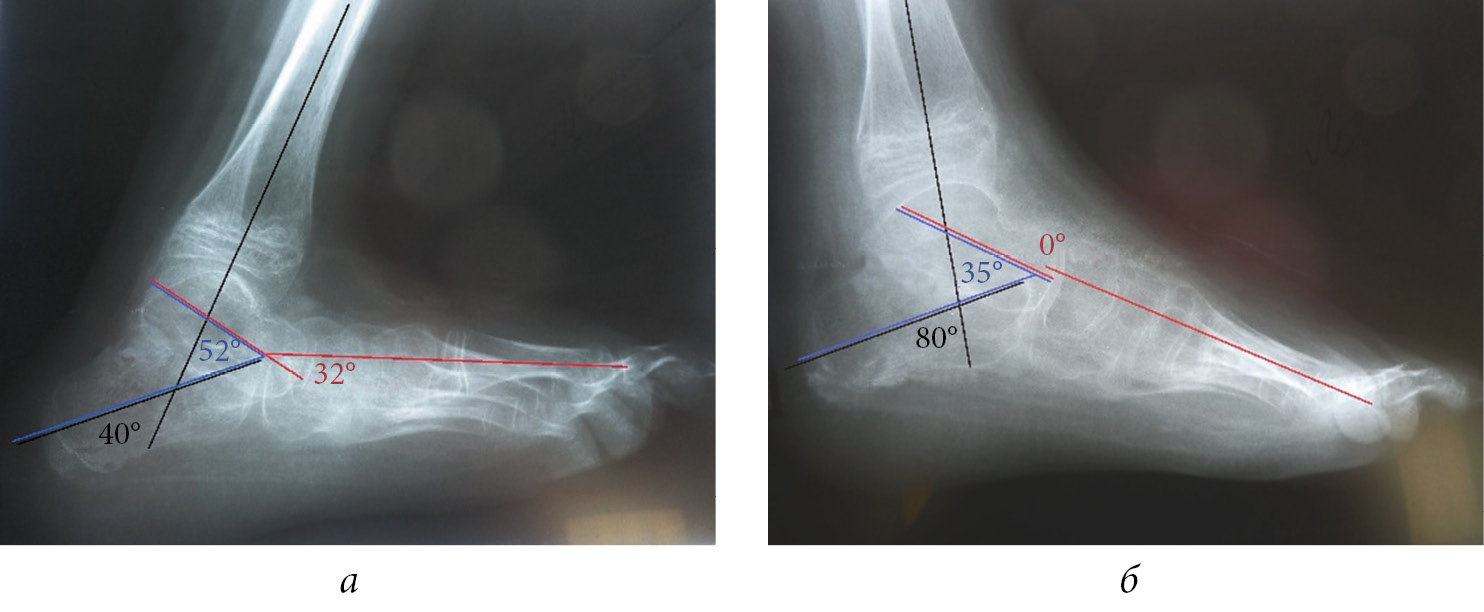

Clinical example (Fig. 2). Patient L., 11 years old. The patient was diagnosed with myelocele and neurogenic calcaneal deformity of the left foot. He complained of difficulty in walking, with support on his left heel bone. Clinically, the left foot was extended at 30°. Active foot movements are possible only with foot extension. The strength of the left tibial muscles was 5, 0, 0, 2, and 2 points in the anterior tibial muscle, peroneal (short and long) muscles, flexors and extensors of the toes, posterior tibial muscle, and a posterior group of tibial muscles, respectively. The foot was passively brought to the middle position “springy”, but not maintained. Ankle flexion was impossible. Radiograph of the left foot showed calcaneal deformity, the vertical position of the calcaneus, 40° for the calcaneotibial angle, 32° for Meary’s angle, and 52° for the sagittal astragalocalcanean angle. One-stage correction of the deformity was performed after considering the possible passive correction of the foot to the middle position and the child’s age. The release of the foot joints (subtalar, astragaloscaphoid, calcaneocuboid, and cuneonavicular) was performed with grafting of the tendon of the anterior tibial muscle to the calcaneal tubercle; fixation of the foot with wires with slight hypercorrection (20° bending of the foot for 2 months) was performed. The foot is fixed in the splint after surgical hardware removal. Clinically, the foot is in the middle position, with support on the entire plantar surface of the foot. The X-ray image shows improvement in the osteo-articular relations in the foot, calcaneotibial angle of 80°, Meary’s angle of 0°, and sagittal astragalocalcanean angle of 35°.

Fig. 2. Patient L., 11 years old, with a diagnosis is neurogenic calcaneal deformity of the left foot: a — radiograph of the left foot in lateral projection upon admission: calcaneotibial angle is 40°, Meary’s angle is 32°, sagittal astragalocalcanean angle is 52°; b — radiograph of the left foot in lateral projection after the surgical treatment: calcaneotibial angle is 80°, Meary’s angle is 0°, sagittal astragalocalcanean angle is 35°